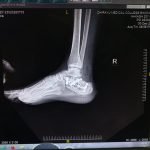

Orthopaedic Surgeon | Arthroscopy & Joint Replacement Specialist

Dr. Aditya Tripathi is a dedicated and skilled Orthopaedic Surgeon specializing in sports injuries, arthroscopy, and joint care. Known for his clinical precision, ethical practice, and patient-first approach, he focuses on helping patients regain mobility, strength, and confidence through evidence-based orthopaedic treatment. His academic background and hands-on clinical training reflect a strong foundation and a commitment to excellence in orthopaedic care.

Dr. Aditya Tripathi is widely appreciated by patients for his clear communication, honest medical guidance, and personalized treatment approach. His expertise in managing ACL tears, ligament injuries, shoulder conditions, and sports-related injuries makes him a trusted choice for comprehensive orthopaedic and sports injury care. Patients value his attention to detail, compassionate care, and focus on long-term recovery—establishing him as a reliable and respected orthopaedic specialist.

- Fracture Treatment